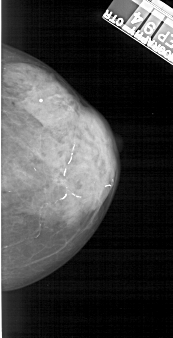

A_1223_1.RIGHT_MLO

RIGHT_CC LINES 4726 PIXELS_PER_LINE 2416 BITS_PER_PIXEL 12 RESOLUTION 43.5 NON_OVERLAY

RIGHT_MLO LINES 5281 PIXELS_PER_LINE 2491 BITS_PER_PIXEL 12 RESOLUTION 43.5 NON_OVERLAY